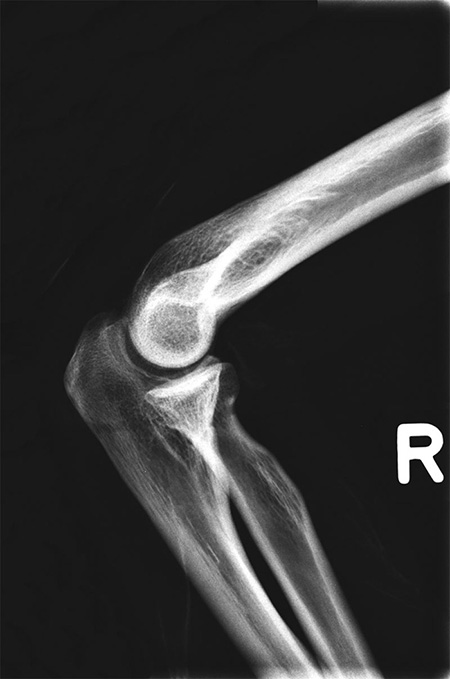

德國(guó)Erler Zimmer 7200天然骨骼全身模體,EZ 7200全身模體包含一個(gè)真實(shí)的人體骨骼,可以像患者一樣拍攝真正的X射線圖像。使用真實(shí)的骨架可以提供最小的導(dǎo)向結(jié)構(gòu),這對(duì)于塑料骨架來說是不可能的。

手肘彎曲向內(nèi)約 90度。髖關(guān)節(jié)分別向前旋轉(zhuǎn)至90度,然后旋轉(zhuǎn)向外達(dá)45度。

雙膝微屈約90度。

7、滿足任意部分進(jìn)行X線/CT掃描,成像效果與真實(shí)人體一致,影像片中能正常分辨出骨齡。

The phantom contains a real human skeleton, which allows taking real X-ray images like in a patient. Using a real skeleton provides even smallest guiding structures which is impossible with a plastic skeleton.